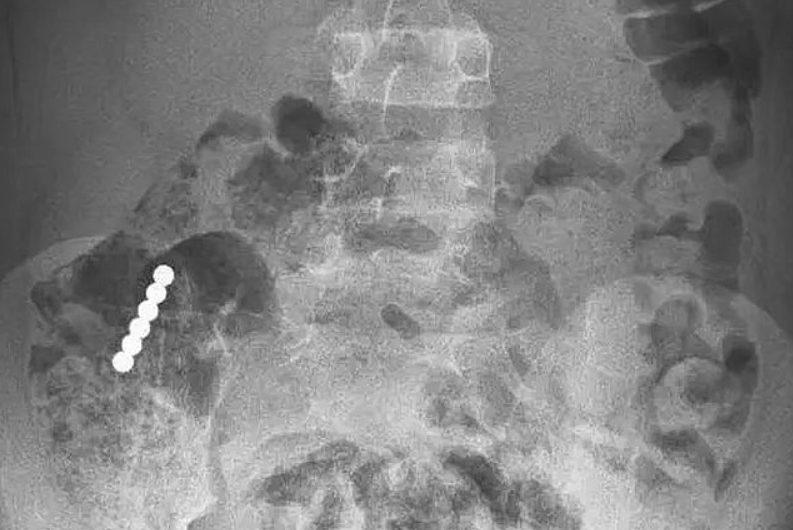

По словам доктора Самеха Татура, специалиста отделения детской и подростковой гастроэнтерологии, в больницу мальчик поступил в хорошем состоянии, у него не было ни рвоты, ни болей. В приемном покое ребенку сделали рентгеноскопию, показавшую несколько небольших магнитов, слипшихся в цепочку и находящихся в районе тонкого кишечника мальчика.

Мальчик был госпитализирован для наблюдения, вскоре выяснилось, что магниты застряли в зоне соединения тонкого кишечника и толстой кишки. Тогда было принято решение провести колоноскопию для извлечения магнитов. Операция проводилась под общим наркозом, врачам удалось обнаружить и извлечь магниты из кишечника ребенка, не прибегая к полостной операции.